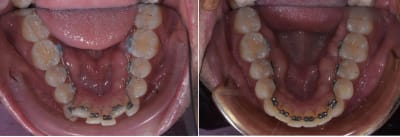

Pour ce patient par exemple quatre mois de traitement et deux files. Cout du matos 200$ et temps entre la prise d'empreinte et la pose moins d'une semaine.

Niveau comfort prédictabilité tu ne peut pas comparé invisalign avec le lingual. Invisalign si tu es bien expérimenté avec le système tu peut commencer à traiter des cas par extractions mais c'est pas toujours top. A coté avec incognito en début d'exercice j'ai fermé trois ou quatre espaces molaire.